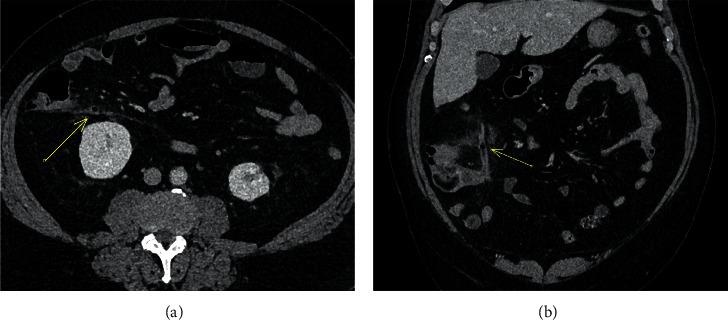

This manuscript aims to investigate the amount of intraluminal gas in acute, nonperforated appendicitis identified on computed tomography (CT) in diagnosing gangrenous appendicitis.

Our study identified 93 patients with nonperforated acute appendicitis who underwent surgery within the stated timeframe. Intraluminal gas in the appendix was identified in 26 patients (28%), of which 54% had macroscopic and/or microscopic evidence of gangrenous appendicitis. This is in contrast to the subgroup of patients who did not have intraluminal gas (72%), of which only 33% had gangrenous appendicitis. The specificity of intraluminal gas for gangrenous appendicitis is 79%, with a negative predictive value of 86% and likelihood ratio of 1.85.

本手稿旨在研究计算机断层扫描(CT)诊断急性非穿孔性阑尾炎时阑尾腔内气体量在诊断坏疽性阑尾炎中的作用。

我们的研究确定了93例在规定时间内接受手术的非穿孔性急性阑尾炎患者。26例(28%)患者阑尾腔内有气体,其中54%有坏疽性阑尾炎的宏观和/或微观证据。相比之下,阑尾腔内无气体的患者亚组(72%)中,只有33%有坏疽性阑尾炎。腔内气体对坏疽性阑尾炎的特异性为79%,阴性预测值为86%,似然比为1.85。